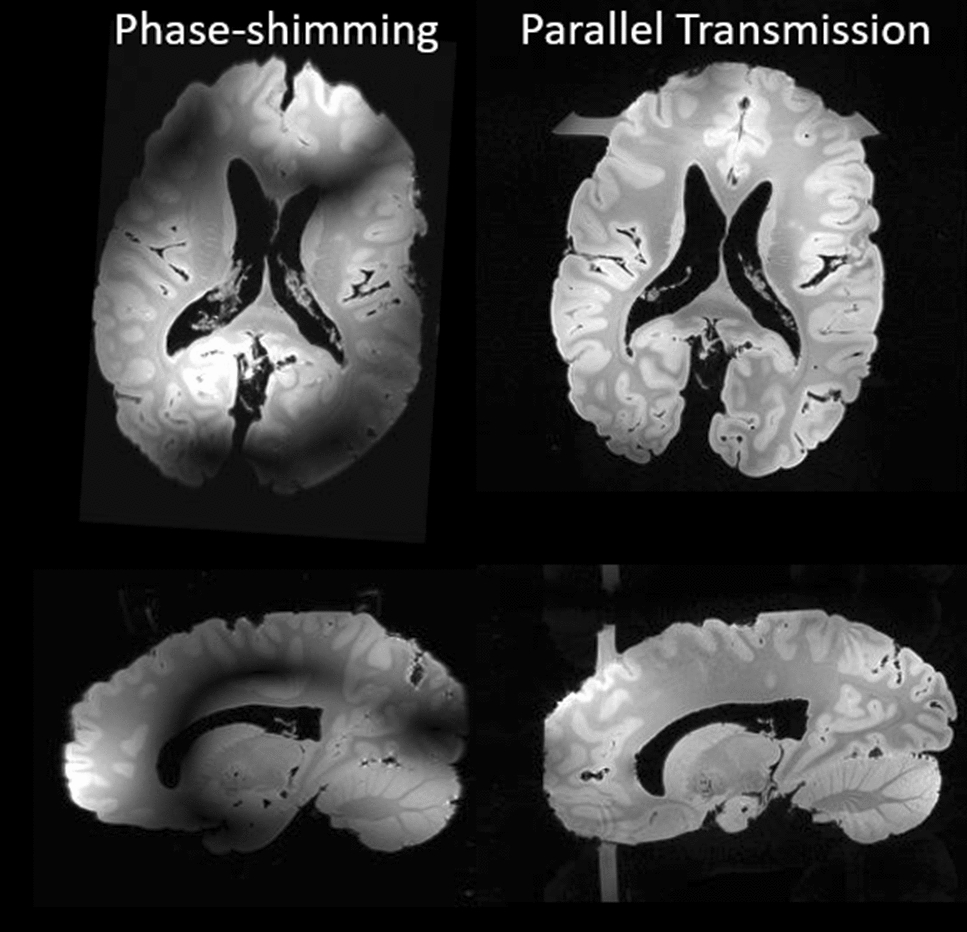

Figure 11 finally illustrates first parallel transmission tests performed with the home-made Iseult RF coil on an ex vivo brain [25]. The result is a 3D GRE acquisition (0.7 mm isotropic resolution, TR = 30 ms, TE = 4.6 ms, FA = 10°, TA = 5 min 30 s, iPAT = 2 × 2). The coil currently combines 15 transceiver and 17 receive-only elements and has a minimized outer diameter (27 cm) to fit in a local B0-shim multi-coil array. The elements are geometrically decoupled via resonant inductive decoupling elements. The coil features two rows of alternate loops and small dipoles (in fact air–gap center-fed microstrips), and a patch at the top of the head. Because only 8 RF amplifiers are for the moment available, the coil operates in a 8Tx-32Rx configuration where 14 transceive elements are coupled in pairs to connect to 7 amplifiers while the last element is connected alone. The combined use of the coil with kT-points parallel transmission pulse design [26] here allowed mitigating the RF field inhomogeneity problem at 11.7 T while, unsurprisingly, phase-shimming did not provide enough degrees of freedom. The horizontal and vertical “bars” in the axial and sagittal views, respectively, are caused by the fixation bar of the ex-vivo brain in its container, which returns some signal with the more broadband kT-point excitation.

Fig. 11.

3D-GRE images acquired with the Iseult pTx RF coil on an ex vivo brain, with phase-shimming (left) and kT-points (right). Axial (top) and sagittal (bottom) slices are shown. The horizontal and vertical bars in the axial and sagittal views respectively, and for the kT-point excitation, result from the excitation of the fixation bar of the ex-vivo brain in its container